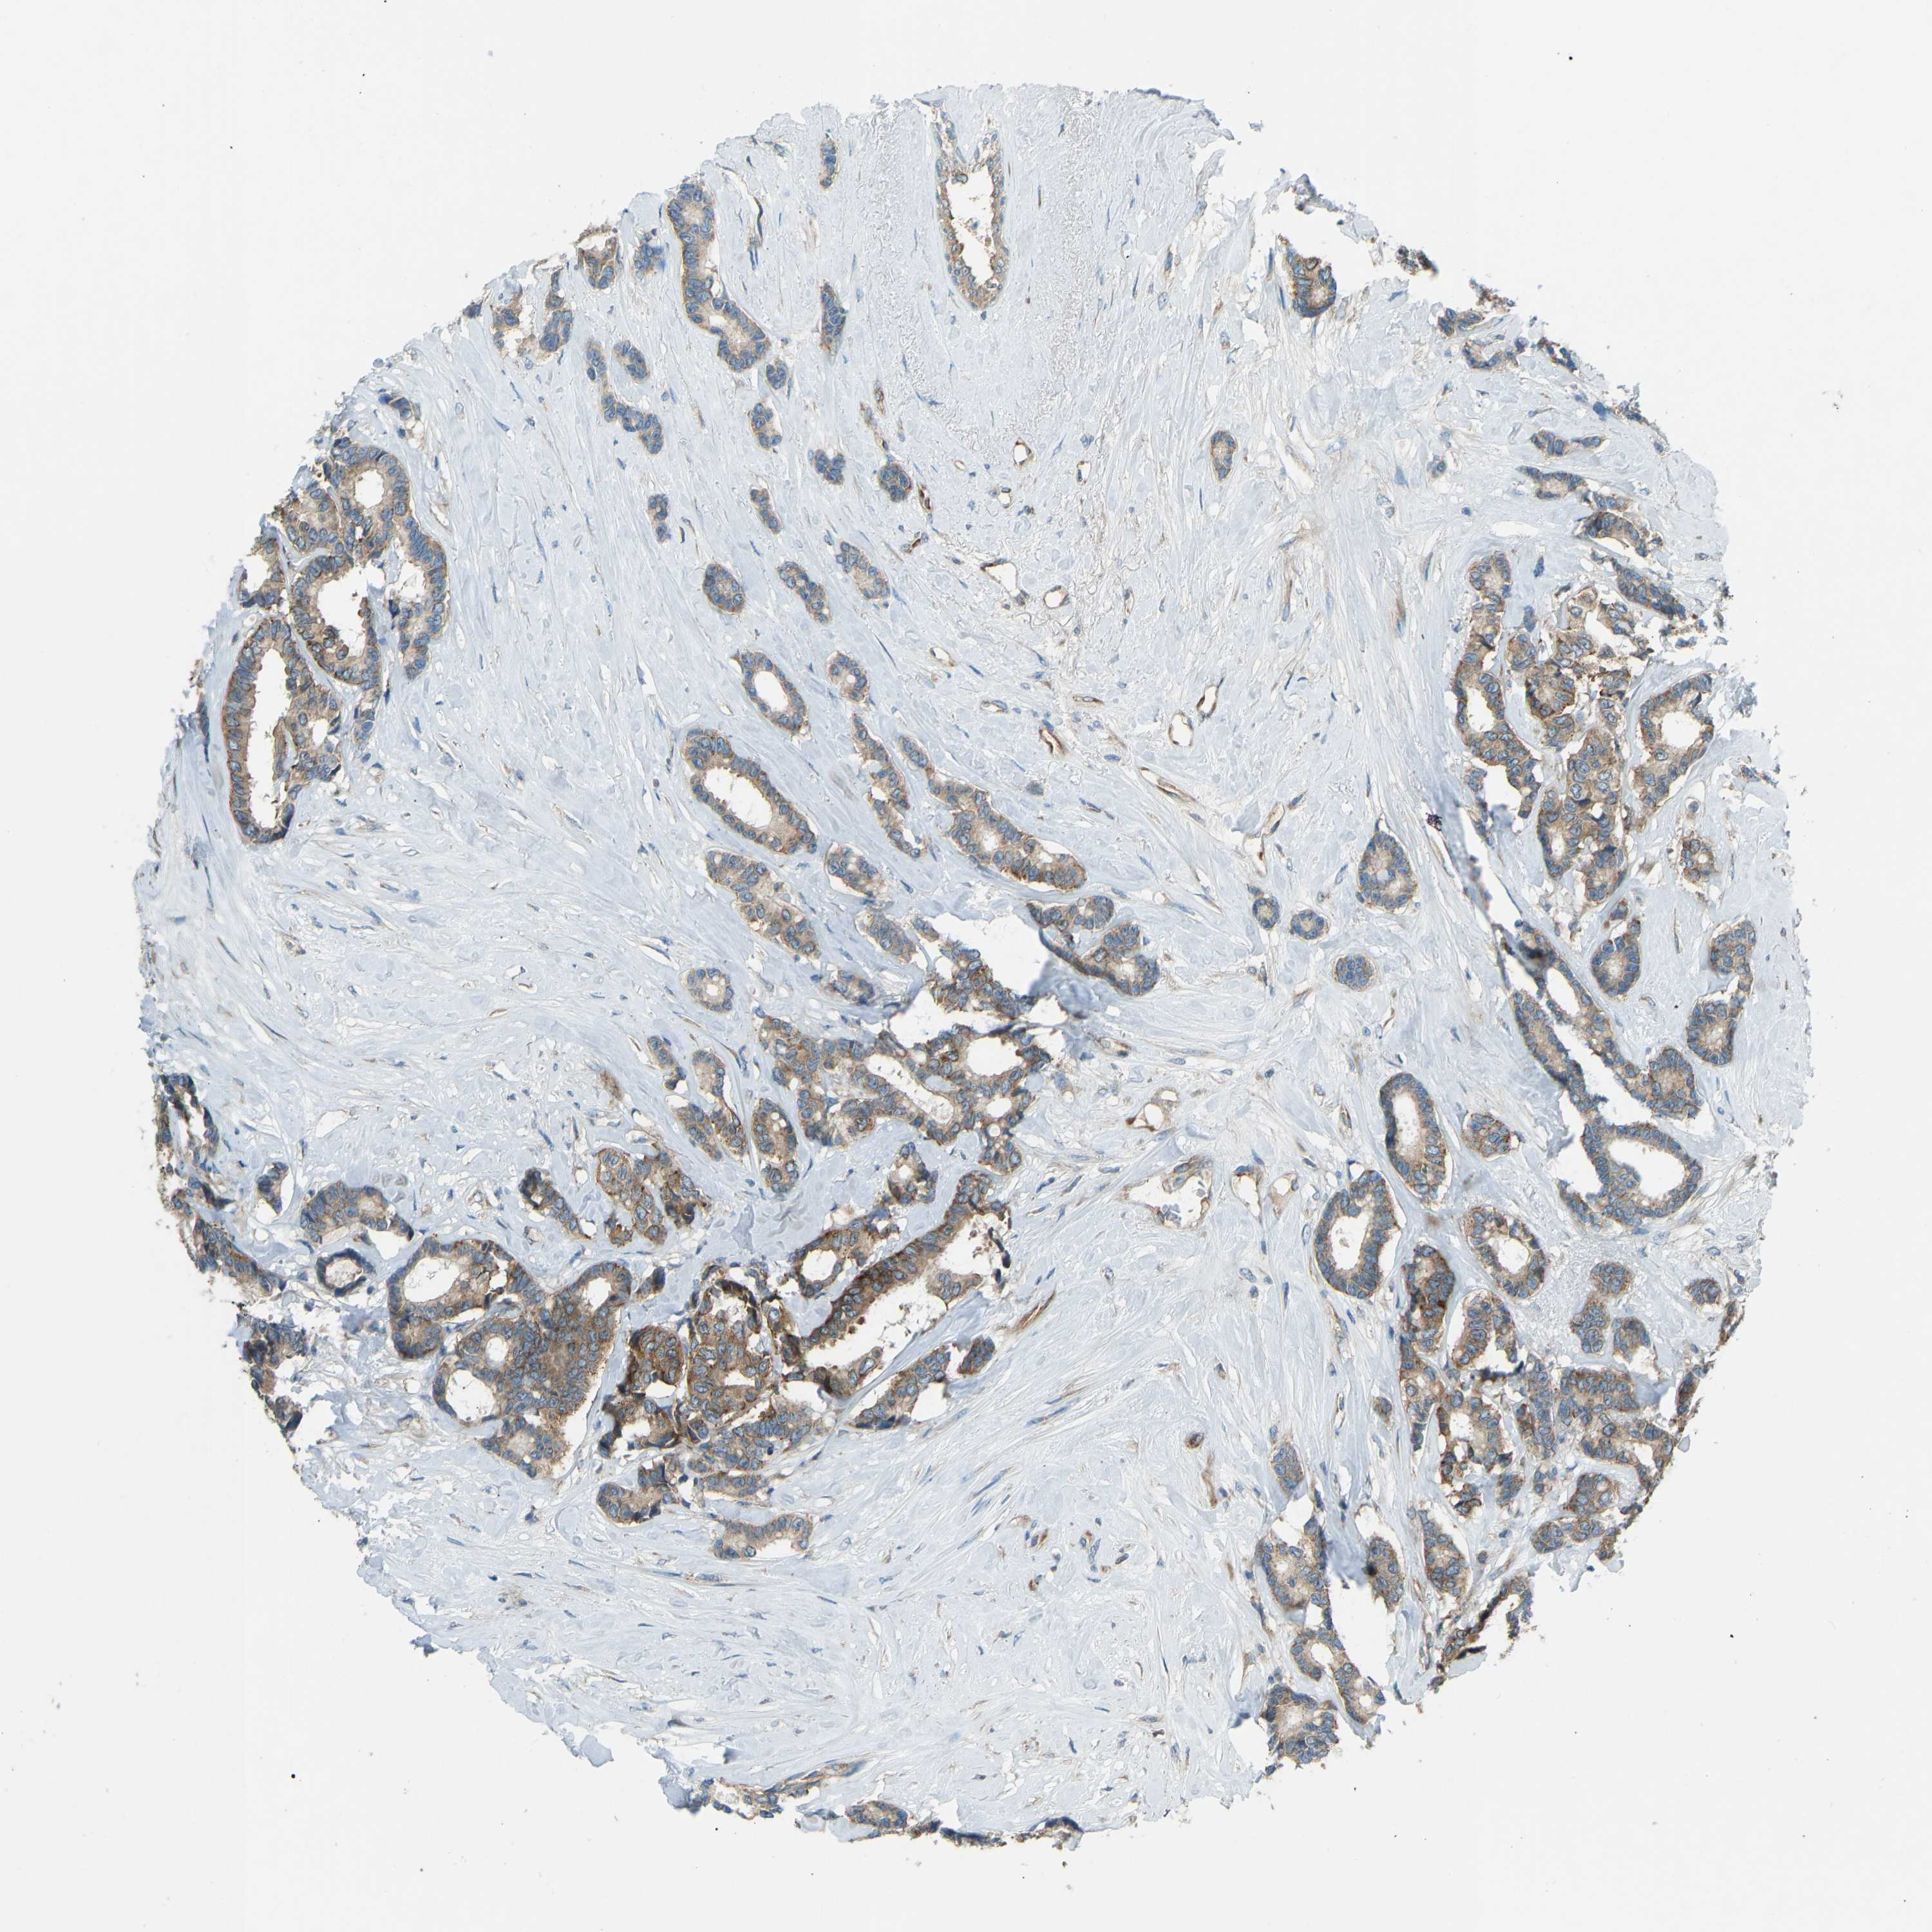

CANCER BREAST CANCER Show tissue menu

BRCA TCGA BRCA VALIDATION PROTEIN EXPRESSION